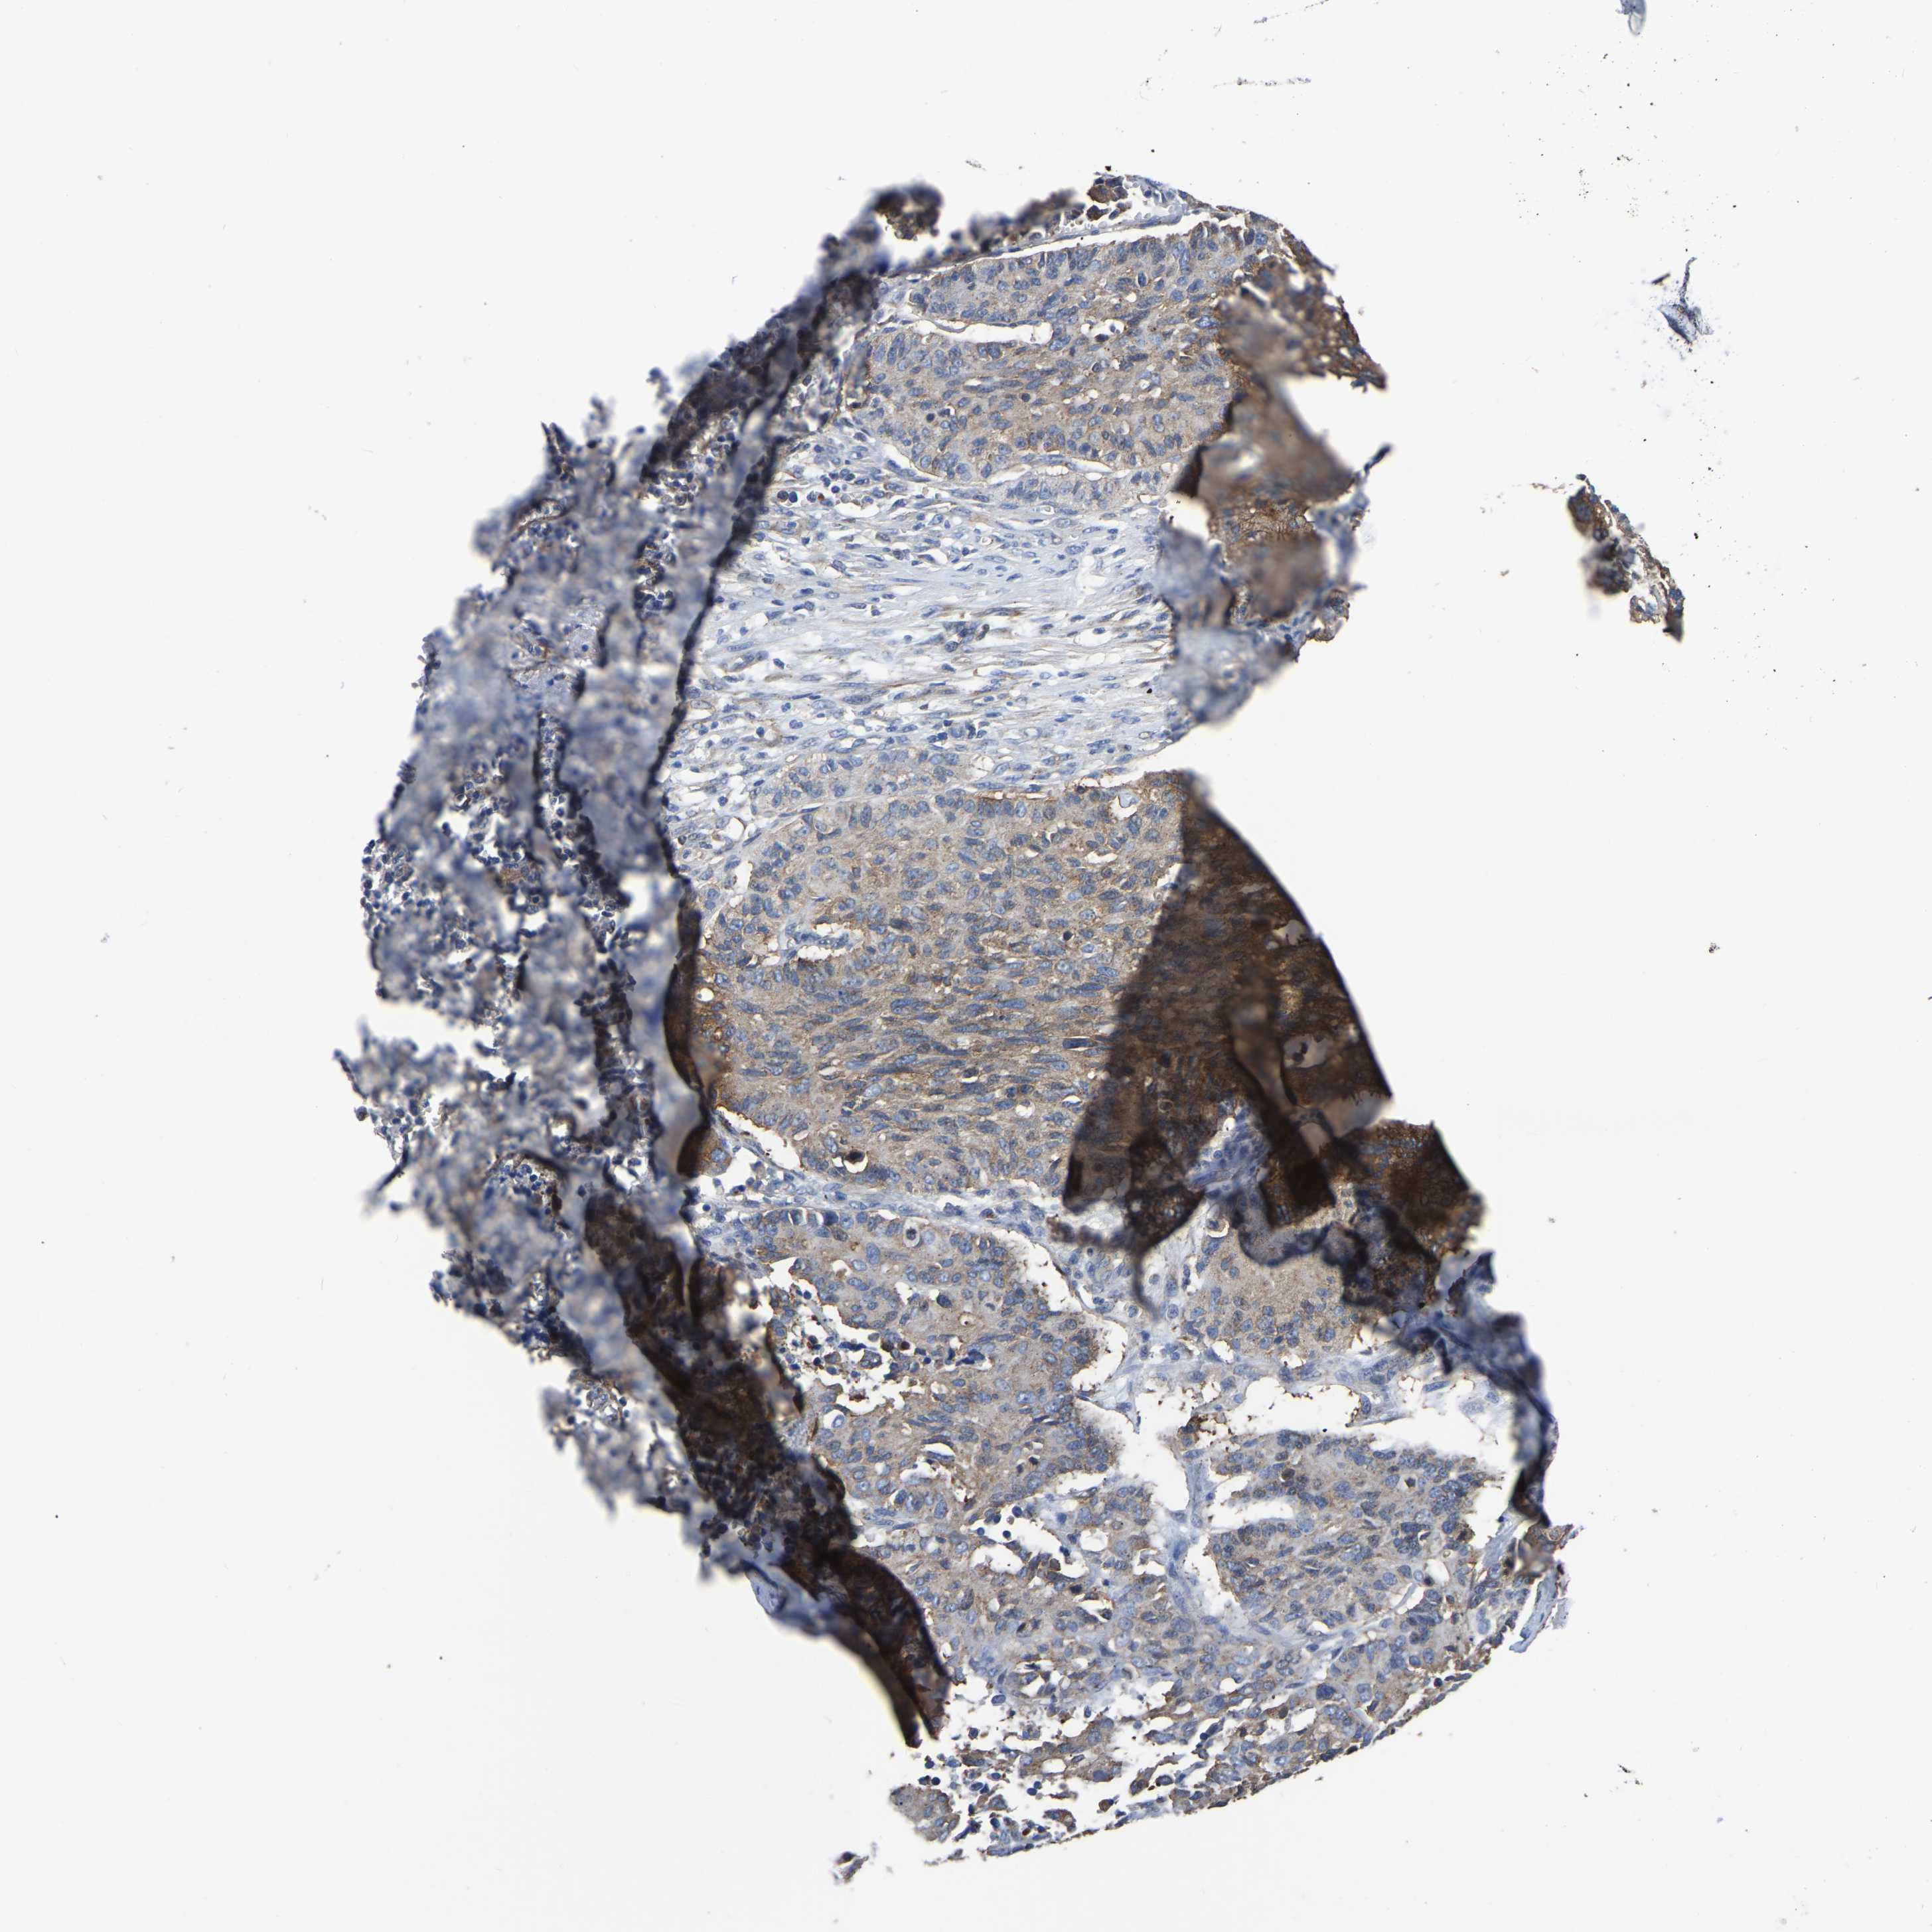

CERVICAL CANCER - Protein expressioni

A mouse-over function shows sample information and annotation data. Click on an image to view it in a full screen mode. Samples can be filtered based on level of antibody staining by selecting one or several of the following categories: high, medium, low and not detected. The assay and annotation is described here.

Note that samples used for immunohistochemistry by the Human Protein Atlas do not correspond to samples in the TCGA dataset.

Antibody stainingi

Antibody staining in the annotated cell types in the current human tissue is reported as not detected, low, medium, or high, based on conventional immunohistochemistry profiling in selected tissues. This score is based on the combination of the staining intensity and fraction of stained cells.

Each image is clickable and will lead to virtual microscopy that enables deeper exploration of all samples and also displays staining intensity scores, fraction scores and subcellular localization as well as patient and tissue information for each sample.

Antibody HPA019473

Staining

High

Medium

Low

Not detected

Intensity

Strong

Moderate

Weak

Negative

Quantity

>75%

75%-25%

<25%

None

Location

Nuclear

Cytoplasmic/membranous

Cytoplasmic/membranous,nuclear

Squamous cell carcinoma, NOS

Adenocarcinoma, NOS